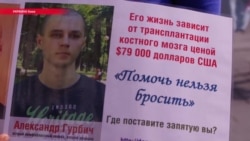

В одной из палаток уже месяц пусто. Рядом – лампадки и цветы, а на палатке – фотография Владимира Скрипова. В конце сентября он умер от рака крови, так и не дождавшись своей очереди на операцию за границей.

Игорь Витошинский – отец онкобольного Эдуарда Витошинского. У его сына острый лейкоз, диагноз поставили еще весной. Тогда же сам Эдуард в своем видеоблоге записал обращение, объявив, что ему нужен донор и деньги на пересадку костного мозга за границей.

"Вот это такая беда, такое горе", – объясняет Витошинский. На химиотерапию Эдуарда, по его словам, родные и близкие с трудом, но собрали нужную сумму. А вот деньги, необходимые на операцию – $110 тысяч – неподъемны для семьи.

"Где в Украине такие деньги есть? Мы уже все, что было, попродавали – и машину, и хату, уже всё, – чуть не плачет Игорь, который уже два месяца спит на надувном матрасе в палатке. – Уже есть донор, мы нашли в Турции донора, уже есть все. Времени нет. Это надо было давно сделать. У нас в Украине не делают такие операции".